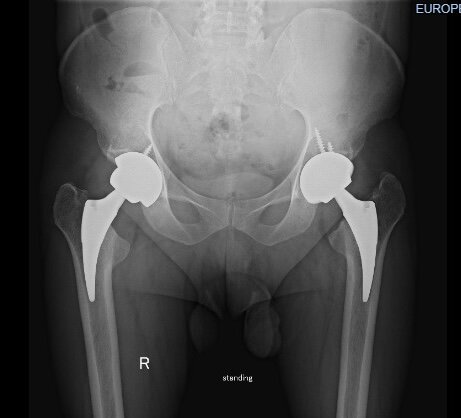

ДВУСТОРОННИЙ НЕКРОЗ ГОЛОВОК БЕДРЕННЫХ КОСТЕЙ ПОСЛЕ КОВИДа

Теперь суставы выглядят вот так

Сегодня был контрольный осмотр - 3 месяца после замены левого сустава, и 1,5 - после правого. Всё идёт штатно. Пациент в целом режим соблюдал (не считая поездки с отцом на охоту на гусей на болота в резиновых сапогах), проходит дистанции до 10 тысяч шагов, плавает, крутит педали.

В принципе, уже можно вести нормальный образ жизни. Нужно поработать над мышцами - они сильно атрофировались, особенно слева, и всё. Как будто не было ни КОВИДа, ни некроза. А суставы эти нас переживут, нет им износа.